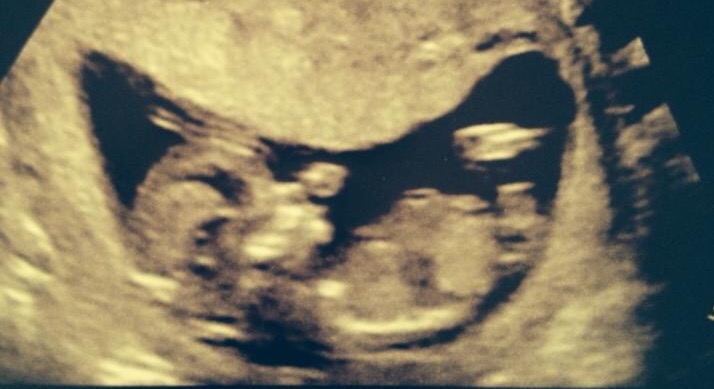

Possibly girl but baby's spine is very curved x

I have put this picture on another page before and all guesses were girl too......this is my SON who is now a big healthy 2 year old! I just wanted to see what people though and if they were right. When I started reading up on nub theory I looked at my old scans and to be honest I would have said girl too for this picture so some are very hard to tell I guess depending on the picture.....I just wish my scan pics were a bit more obvious as this current baby is driving me nuts no knowing xx